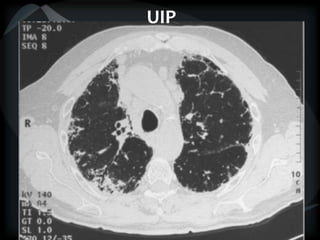

HRCT

RETICULAR PATTERN - UIP

 peripheral reticular lines / inter and intralobular septae

 honeycomb

 Traction bronchiectasis

 None or minimal ground glass

 Gradient increasing from apex to base

 Skip areas

 Diagnostic accuracy high

 Idiopathic

 Familial

 CVD - RA

 Drugs – NFT, Busulphan

 Asbestosis = basilar – bands – pleural calcification

 Chronic HP = upper and midzones

 Hermansky-Pudlak syndrome